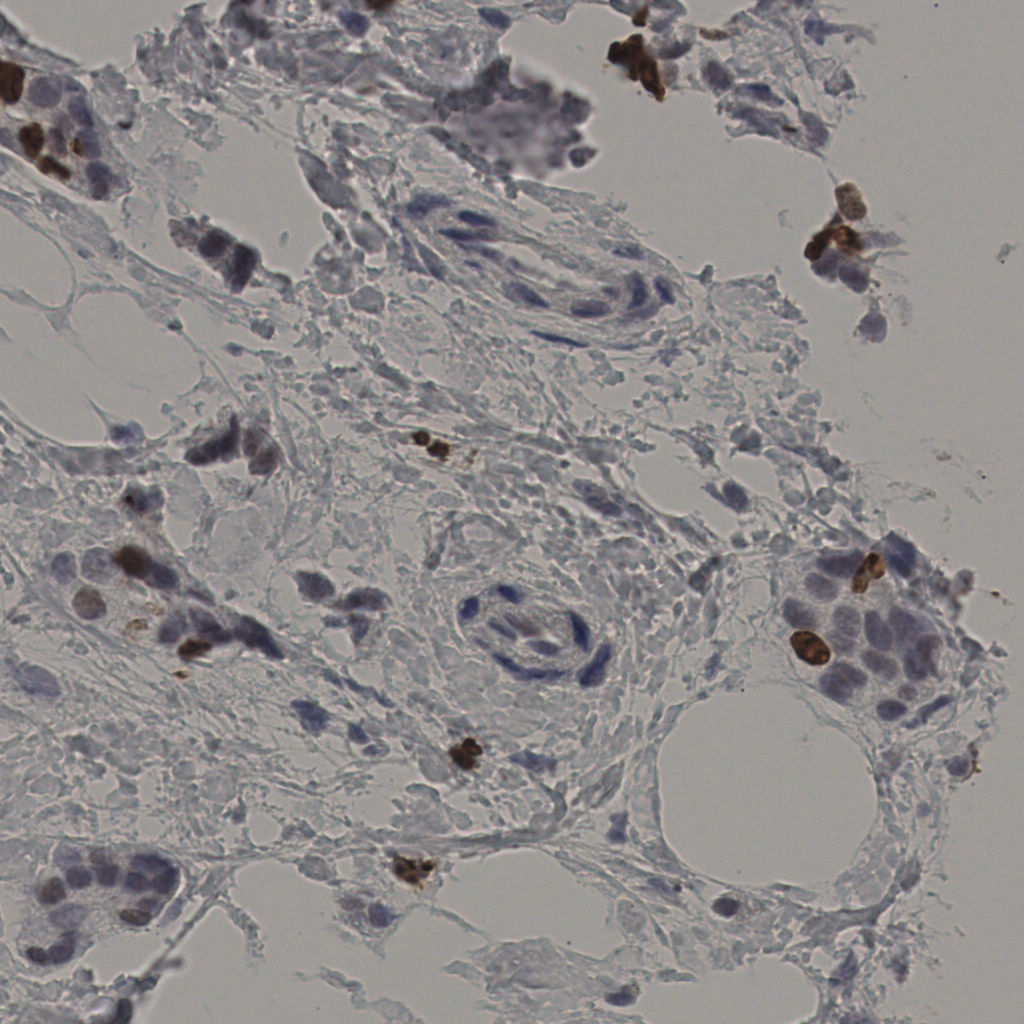

缩略图

标记后

标记前